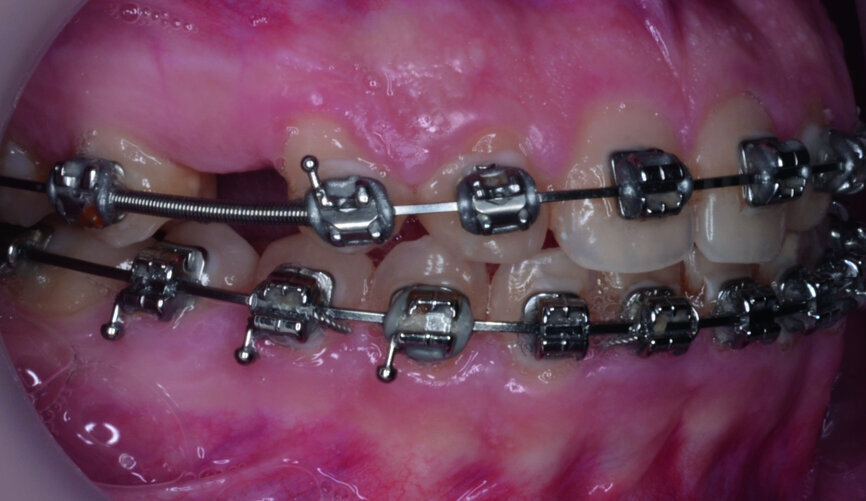

- Implants space opening: substitute laterals with canines (Figs. 23–25) and substitute canines with first premolars (Figs. 26–28).